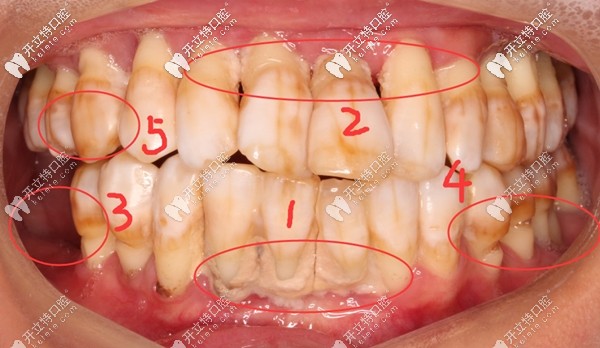

其实邓老师的满口牙齿基本都在,但,一颗都留不住,因为全部都摇摇欲坠,牙根只有很浅一截在牙槽骨内,失去了咀嚼功能。

牙齿问题:①牙结石沉积 ;②重度牙周炎引起牙龈萎缩,牙根暴露;③牙齿楔形缺损;④四环素牙;⑤牙齿晚上痛到影响睡觉,痛的程度感觉已经无法忍受了;⑥轻轻咬一点东西牙齿都在里面动....